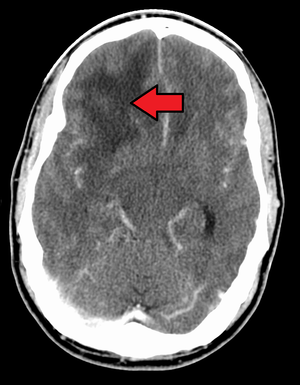

ويمكن أن تشمل الاختبارات، التصوير المقطعي المحوسب والتصوير المقطعي بالإصدار البوزيتروني.

قد يتم إجراء خزعة باستخدام إبرة بالتوضيع التجسيمي للأورام الدبقية في المناطق التي يصعب الوصول إليها أو المناطق الحساسة جدًا داخل الدماغ التي قد تتضرر من أي عملية أكثر توسعًا. خلال خزعة إبرة التوضيع التجسيمي، يحفر جراح الأعصاب ثقبًا صغيرًا في الجمجمة. ثم يتم إدخال إبرة رفيعة من خلال ثقب. تتم إزالة الأنسجة من خلال الإبرة، والتي كثيرًا ما يتم توجيهها باستخدام التصوير المقطعي المحوسب أو المسح الضوئي بالتصوير بالرنين المغناطيسي. ثم يتم تحليل عينة الخزعة تحت المجهر لتحديد ما إذا كانت سرطانية أو حميدة.